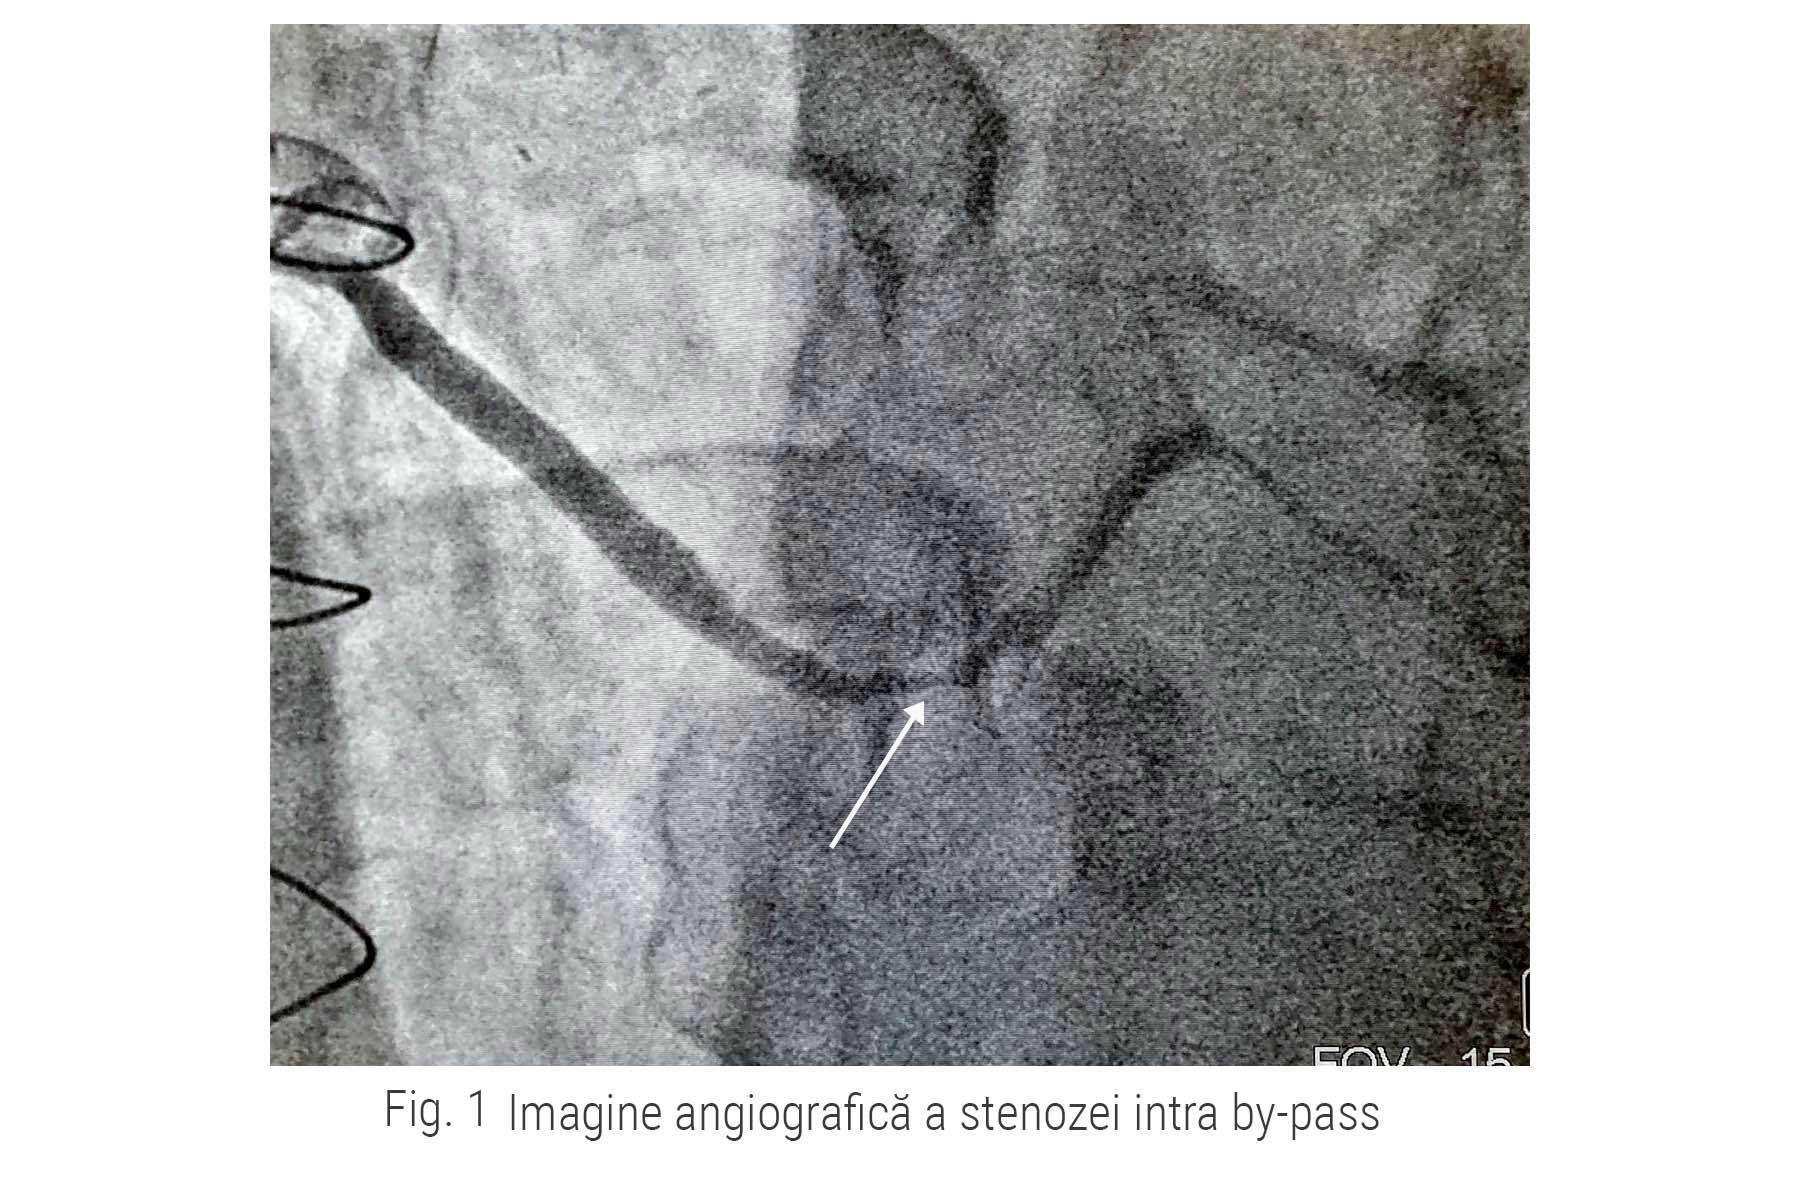

Astfel, doctorul Adnan Mustafa, medic cardiolog intervenționist la ARES Constanța a efectuat coronarografia care a evidențiat o nouă stenoză severă la nivelul unuia dintre by-passurile (fig.1) efectuate în anul 2002.